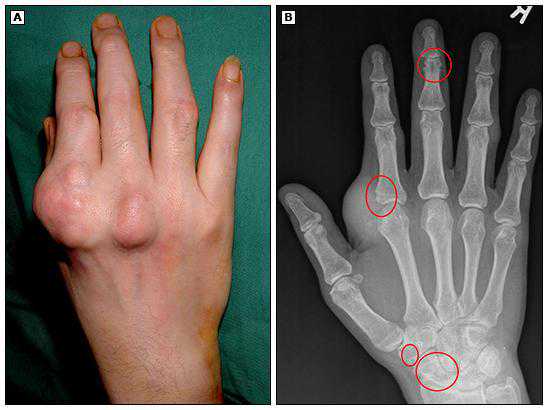

⑥痛风石

这种就比较恶心了!

痛风这个病在古代被称为富人才能得的病,痛风石也一度被称为“富贵石”!

此病常见于尿酸高的患者,尿酸盐结晶后沉积于皮下形成质地坚硬的包块,急性的痛风发作可能仅伴有关节周围肿胀、皮肤发红发热、局部疼痛,慢性的痛风石患者,肿块可能不伴有疼痛,需要鉴别。

治疗上对于明显痛风石形成影响关节活动度的患者,建议手术清理痛风石!